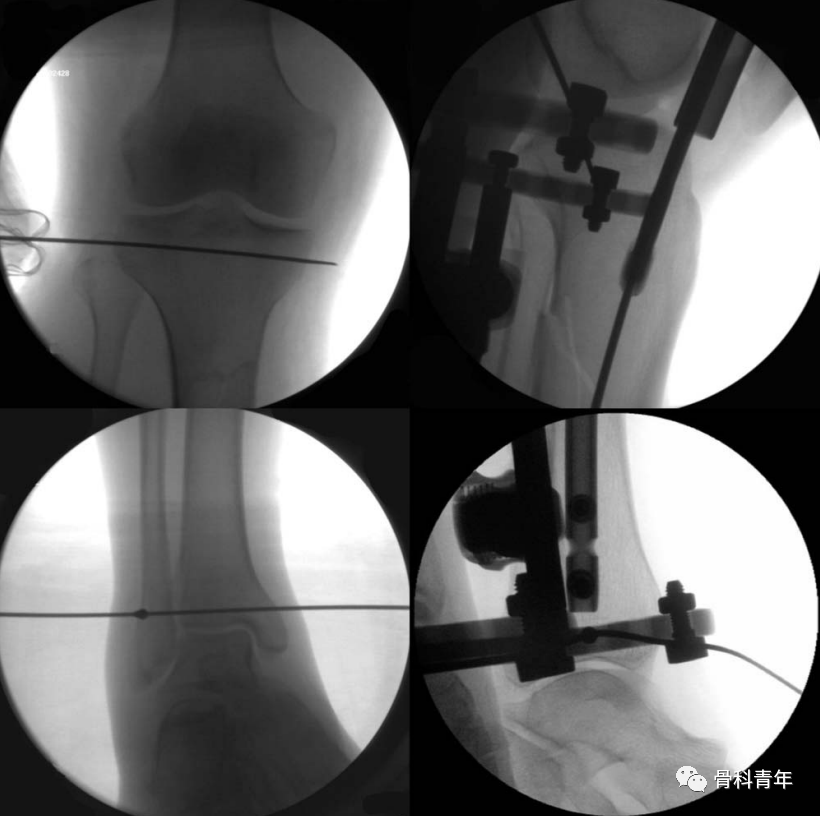

通过在胫骨平台下方1cm,平台偏后部置入一根钢丝,另一根钢丝置入踝关节软骨下骨处,钢丝连接外侧2/3碳纤维环形架,施加110kg拉力形成张力。由于钢丝非中心置入,因此在轴向撑开时,骨折断端可能会向后成角,需要在中部后方垫消毒巾,并巾钳固定。

该外架为碳纤维,术中不影响透视,且该2/3外架,将连接杆置于小腿后方,给髓内钉的内外置钉留出空间。